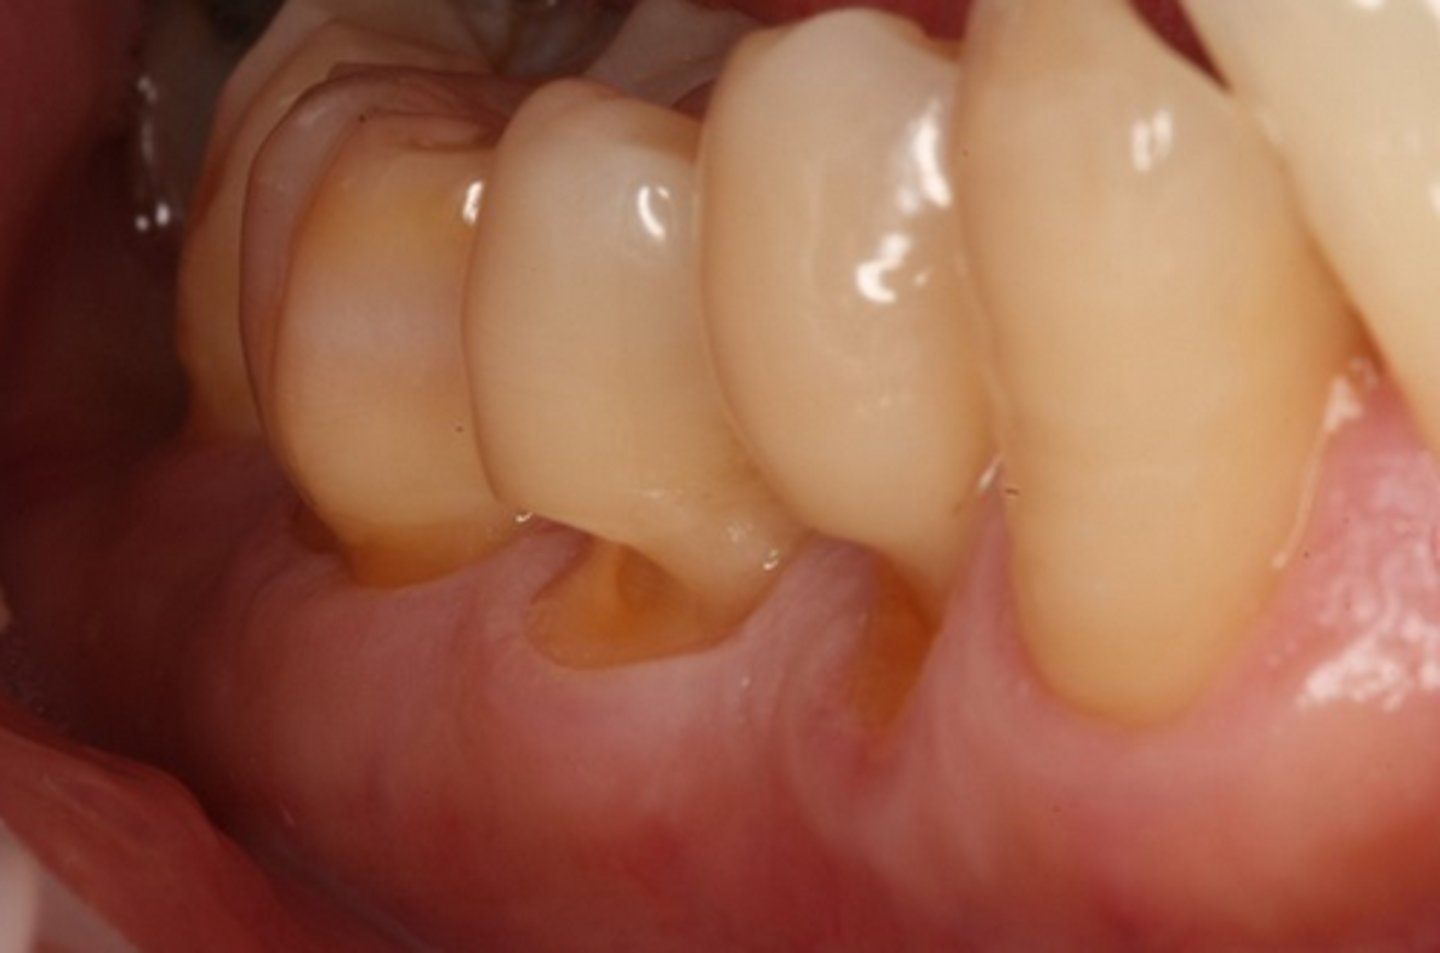

abfraction

Condition that results in "V" shaped notches in the cervical third of the tooth often caused by occlusal forces.

<p>Condition that results in "V" shaped notches in the cervical third of the tooth often caused by occlusal forces.</p>